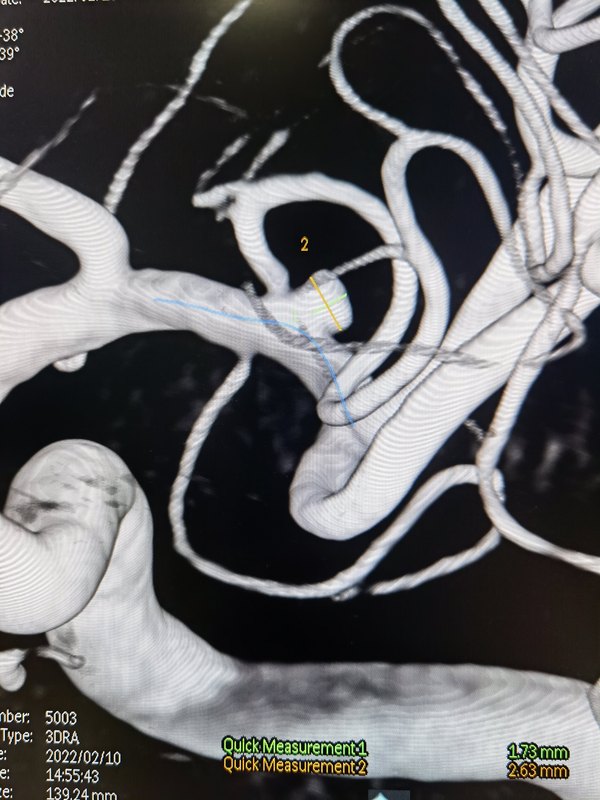

身體有有問題抗過過年都開始檢查身體看病了,發(fā)揮傳統(tǒng)優(yōu)勢(shì)介入技術(shù)(腦動(dòng)脈瘤支架輔助彈簧圈栓塞術(shù)),開發(fā)介入新技術(shù)(顱內(nèi)動(dòng)脈狹窄藥物球囊成形術(shù)-介入無植入),服務(wù)患者,做到安全,省錢,可靠,長期效果好[福]病例一病例二藥物球囊血管內(nèi)介入成形治療顱內(nèi)動(dòng)脈狹窄,無需植入支架,遠(yuǎn)期效果好

顱內(nèi)動(dòng)脈瘤血流導(dǎo)向裝置治療越來越成為側(cè)壁動(dòng)脈瘤的首選治療方式,skyxega裝置由我院作為全國牽頭單位,好釋放,貼壁好,效果好,還免費(fèi)。 腦動(dòng)脈瘤被喻為“腦內(nèi)非定時(shí)炸彈”,一旦破裂死亡率達(dá)30%。 建議:定期體檢,發(fā)現(xiàn)炸彈及時(shí)拆除?